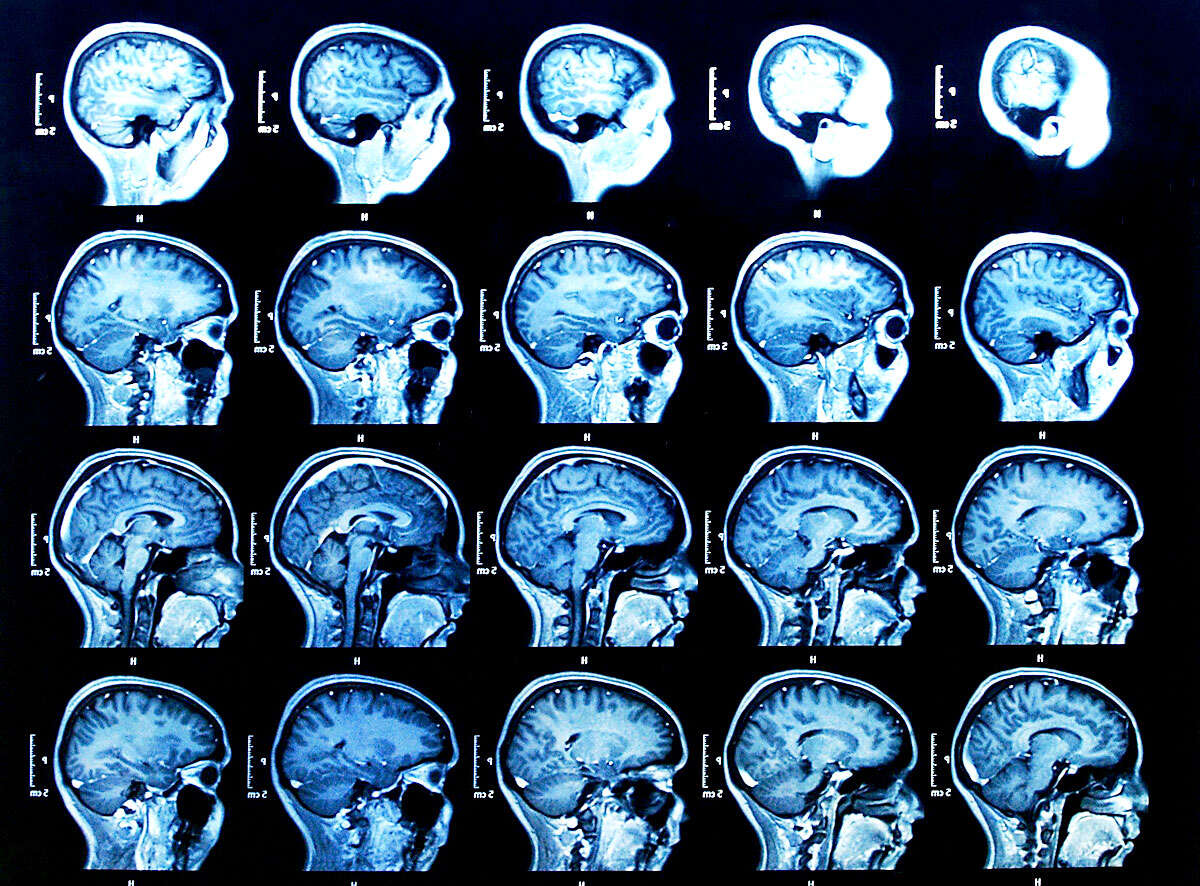

אומרים שהמוח הוא האיבר הכי חיוני בגוף האדם. האומנם? כולנו הולכים מבקרים מידי פעם אצל הרופא בכדי לטפל במחלות שונות שתוקפות אותנו. אבל חולה אחד בצרפת קיבל את השוק של חייו כאשר הלך לטפל בכאבים ברגלו – הרופאים הודיעו לו כי חסר לו חצי מוח.

ליאוניל פוילנט, שחקר את מוחו של האיש לאחר הגילוי המדהים, ציין בכת העת הרפואי: "כל המוח שלו הצטמצם - האונות הקדמיות, הקודקודית, הזמניות והעורפיות – בשני הצדדים גם בימין וגם בשמאל. האזורים הללו במוח שולטים על תנועה, רגישויות, שפה, ראייה, רגשות ופונקציות קוגנטיביות נוספות."

הרופאים הסבירו כי התופעה היא הפרעה שלאחר הלידה, שנגרמה ממים בתוך המוח. עם השנים הצטמצם מוחו של הצרפתי ב-50%-75%. כעת, שמונה שנים לאחר הגילוי והטיפול שניתן לו, מאמינים הרופאים כי הוא ניצל מכיוון שמוחו ארגן את עצמו מחדש. רוב הנוזלים שנאגרו במוחו נעלמו וכיום חי האיש באופן נורמאלי.